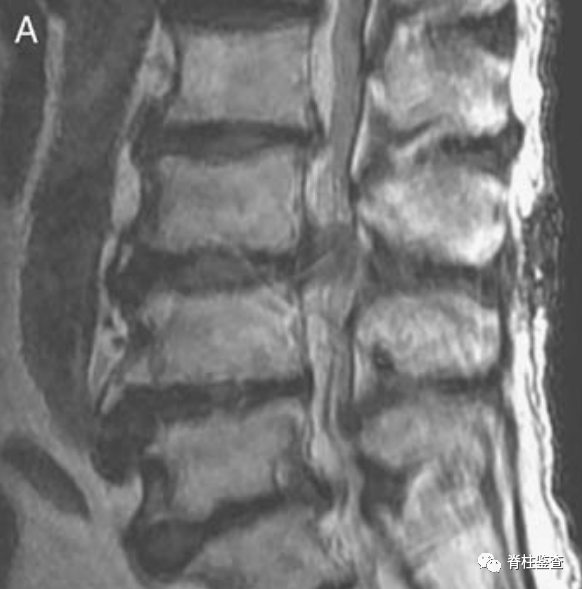

上次手术的椎板切除使此次手术无需进一步切除椎板(黑色↓)

术后第1天显示,椎间盘充分移除;MR图像中的瘢痕组织限制了硬膜囊的充分扩张(白色↓)。